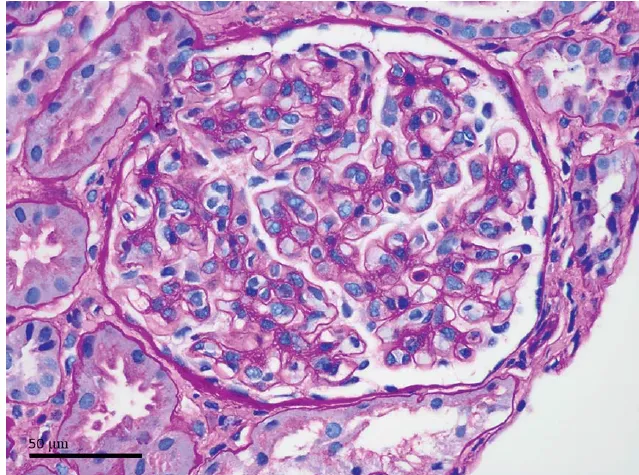

DRC “indeterminada” raramente é falta de diagnóstico — quase sempre é falta de método. Tempo de evolução, urina bem avaliada, USG renal e história clínica dirigida mudam conduta e evitam erros comuns na prática nefrológica.